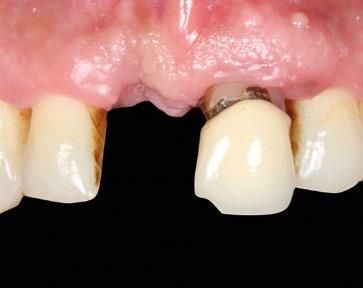

Paciente mujer de 35 años, con amplia exposición gingival en sonrisa y alta demanda estética (Fig. 1, 2).

Su solicitud inicial es volver a blanquear el 21, que había sido previamente endodonciado y había recibido sucesivos tratamientos blanqueadores que habían recidivado. Refiere ligera molestia en la papila interincisiva. En la exploración radiográfica intraoral 1 2

se aprecia una extensa reabsorción radicular interna, con el consiguiente defecto óseo, que se confirma con un CBCT (Fig. 3, 4, 5). Se informa a la paciente del riesgo de fractura espontanea. Esta solicita solucionar el problema antes de que avance más.

En estos casos es crítica la gestión de los tejidos blandos para compensar la pérdida del soporte por parte del trayecto supracrestal de la raíz con en ITC y provisionalización inmediata.

El plan de tratamiento propuesto es, previa planificación digital, la reposición postextracción del 21, relleno del gap bucal, injerto conectivo subepitelial y provisionalización inmediata. Tras 4 meses iniciar la fase de acondicionamiento final del tejido blando y a los 6 meses prótesis definitiva. Planificación digital de la posición ideal del implante y fabricación de la guía quirúrgica y corona provisional (Fig. 6 y 7).